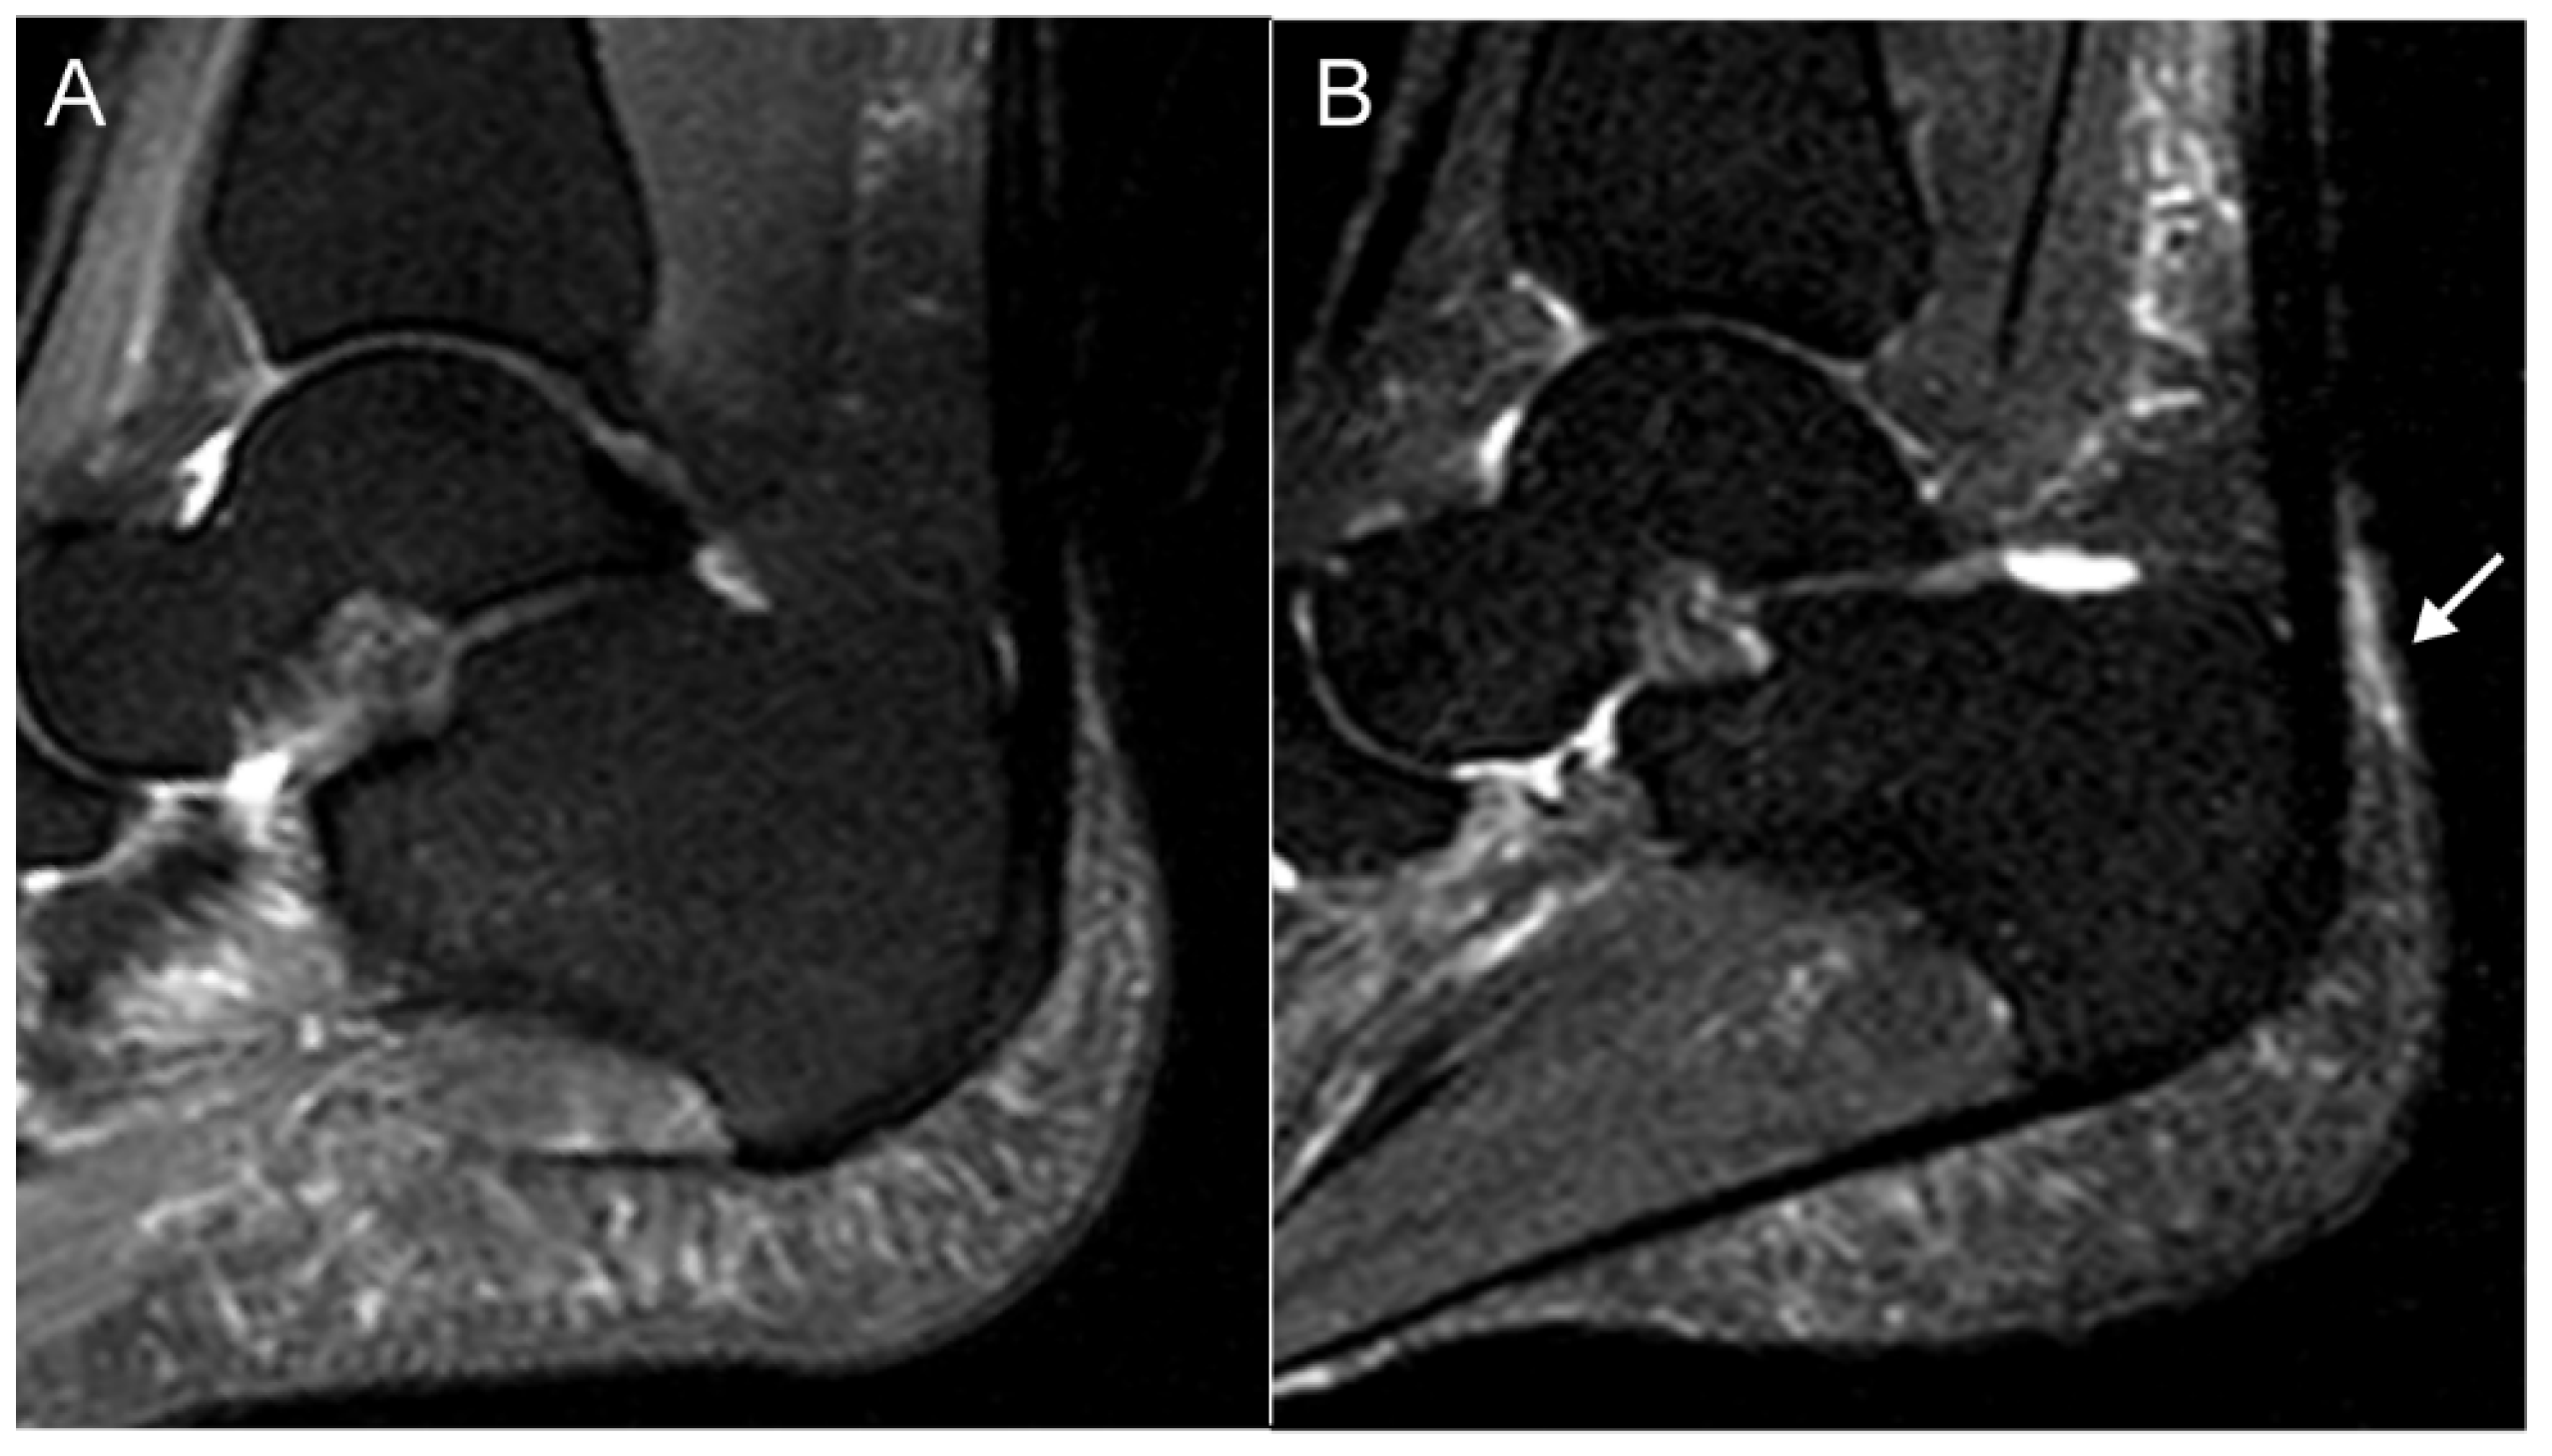

- Mathew, A.J.; Krabbe, S.; Eshed, I.; Gandjbakhch, F.; Bird, P.; Pedersen, S.J.; Stoenoiu, M.S.; Foltz, V.; Glinatsi, D.; Lambert, R.G.; et al. The OMERACT MRI in Enthesitis Initiative: Definitions of Key Pathologies, Suggested MRI Sequences and Novel Heel Enthesitis Scoring System (HEMRIS). J. Rheumatol. 2019, 46, 1232–1238. [Google Scholar] [CrossRef] [PubMed]

- Mathew, A.J.; Krabbe, S.; Eshed, I.; Lambert, R.G.; Laredo, J.-D.; Maksymowych, W.P.; Gandjbakhch, F.; Emad, Y.; Stoenoiu, M.S.; Foltz, V.; et al. Atlas of the OMERACT Heel Enthesitis MRI Scoring System (HEMRIS). RMD Open 2020, 6, e001150. [Google Scholar] [CrossRef] [PubMed]